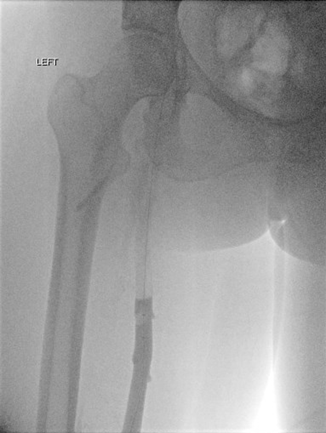

Acceso poplíteo; vista de posición decúbito prono de un trombo oclusivo agudo en la vena poplítea izquierda y en la vena femoral.

Acceso poplíteo; vista de posición decúbito prono de un trombo oclusivo agudo en la vena femoral izquierda y en las venas ilíacas.